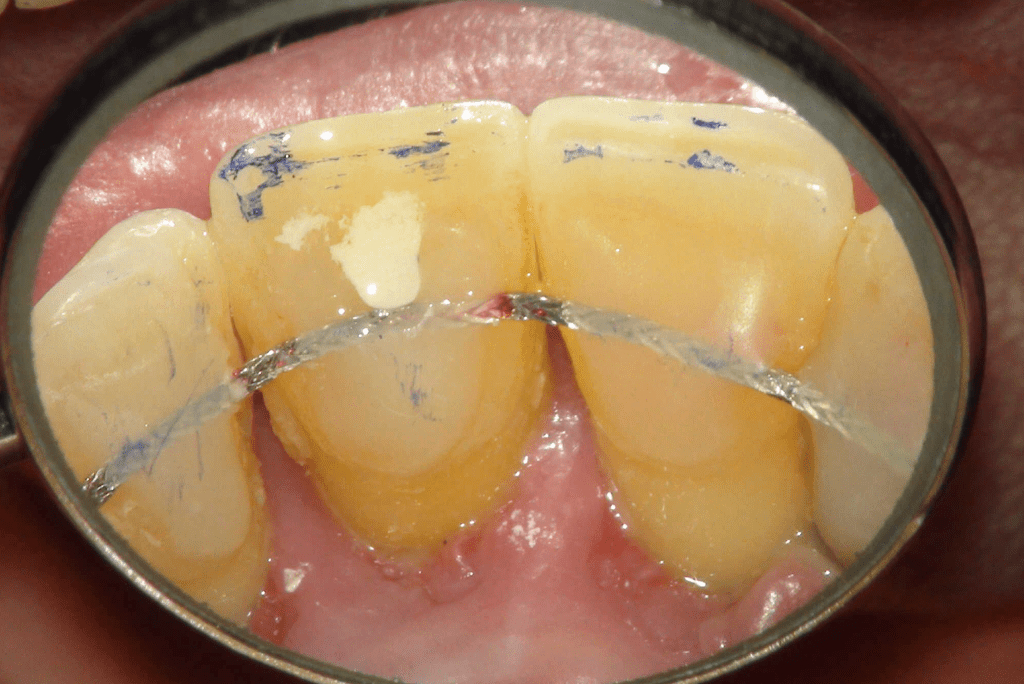

Pulpotomía biodentine + reco preendio